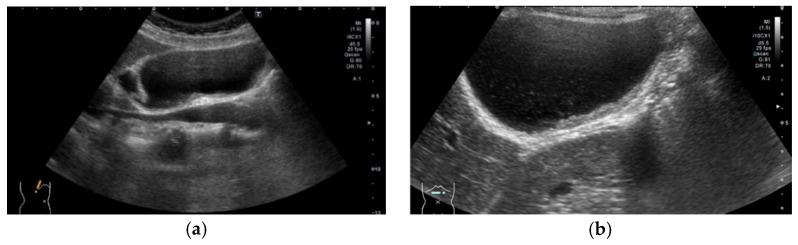

The most important role of ultrasound (US) in the management of gallbladder (GB) lesions is to detect lesions earlier and differentiate them from GB carcinoma (GBC). To avoid overlooking lesions, postural changes and high-frequency transducers with magnified images should be employed. GB lesions are divided into polypoid lesions (GPLs) and wall thickening (GWT). For GPLs, classification into pedunculated and sessile types should be done first. This classification is useful not only for the differential diagnosis but also for the depth diagnosis, as pedunculated carcinomas are confined to the mucosa. Both rapid GB wall blood flow (GWBF) and the irregularity of color signal patterns on Doppler imaging, and heterogeneous enhancement in the venous phase on contrast-enhanced ultrasound (CEUS) suggest GBC. Since GWT occurs in various conditions, subdividing into diffuse and focal forms is important. Unlike diffuse GWT, focal GWT is specific for GB and has a higher incidence of GBC. The discontinuity and irregularity of the innermost hyperechoic layer and irregular or disrupted GB wall layer structure suggest GBC. Rapid GWBF is also useful for the diagnosis of wall-thickened type GBC and pancreaticobiliary maljunction. Detailed B-mode evaluation using high-frequency transducers, combined with Doppler imaging and CEUS, enables a more accurate diagnosis.

超声(US)在胆囊(GB)病变管理中的最重要作用是更早地检测病变并将其与胆囊癌(GBC)区分开来。为避免漏诊病变,应采用体位改变以及具有放大图像的高频探头。GB病变分为息肉样病变(GPLs)和胆囊壁增厚(GWT)。对于GPLs,应首先分为有蒂型和无蒂型。这种分类不仅有助于鉴别诊断,也有助于深度诊断,因为有蒂癌局限于黏膜层。胆囊壁血流(GWBF)快速、多普勒成像时彩色信号模式不规则以及对比增强超声(CEUS)静脉期不均匀强化均提示GBC。由于GWT可在多种情况下出现,将其细分为弥漫性和局灶性形式很重要。与弥漫性GWT不同,局灶性GWT是GB特有的,且GBC发生率更高。最内层高回声层的连续性中断和不规则以及GB壁层结构不规则或破坏提示GBC。快速GWBF对壁增厚型GBC和胰胆管汇合异常的诊断也有帮助。使用高频探头进行详细的B超评估,结合多普勒成像和CEUS,可实现更准确的诊断。